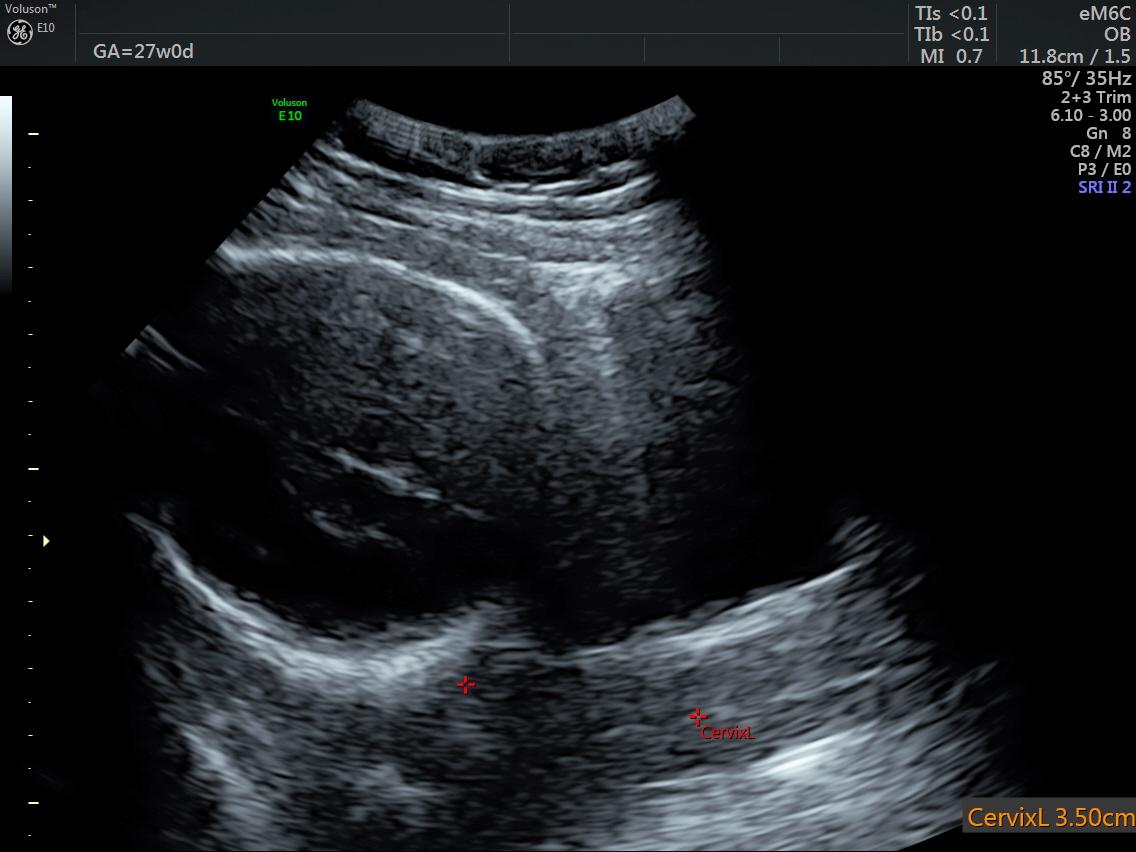

RT AORTIC ARCH_37 Published June 17, 2016 at 1136 × 852 in Rt aortic arch and aberrant left subclavian artery ← Previous Next →